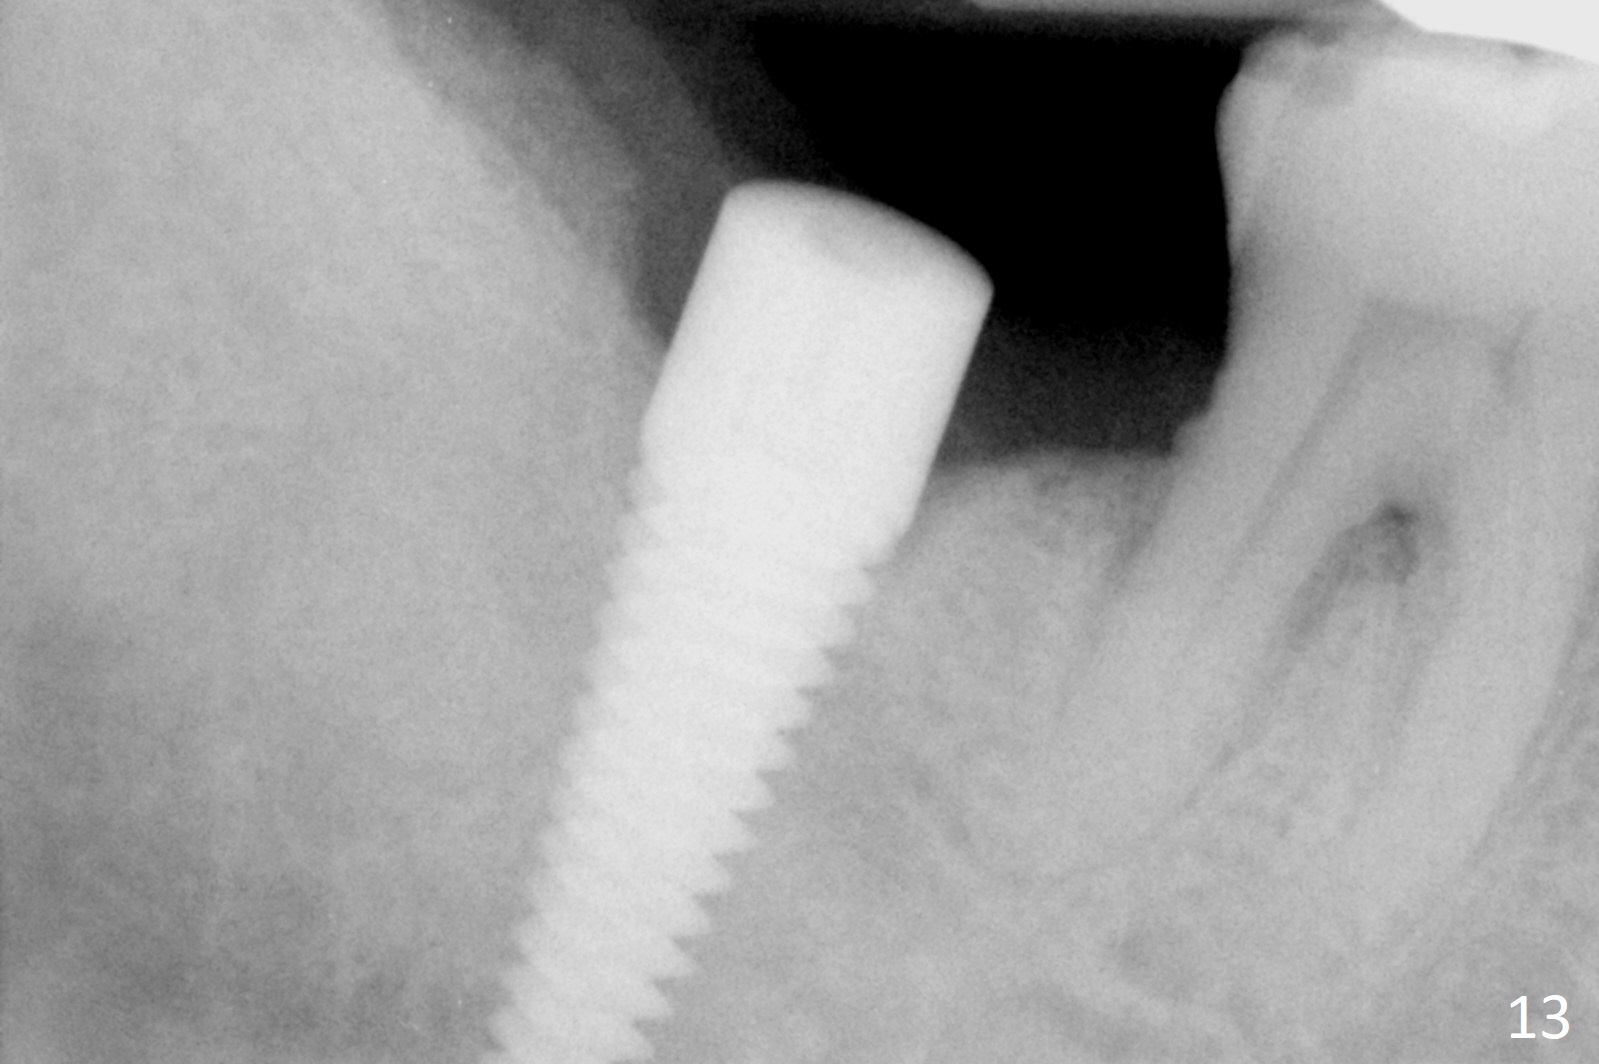

A 50-year-old man, a smoker, presents to clinic with pain of the tooth #15 with apparently occlusal trauma (Fig.1). Two years and three months after #15 extraction, he returns for #31 extraction (Fig.2) and socket preservation (Fig.3). The socket depth is 17 mm along the long axis of the socket 2.5 months post extraction (Fig.4, gingival level). Initial osteotomy is created in the mesial slope of the socket for 14 mm (Fig.5). After sequential osteotomy, a 6x17 mm tap is seated shallower (Fig.6) than the 2 mm drill (Fig.5). Following further osteotomy, a 7x14 mm implant is seated incompletely (Fig.7), which was not found intraop. The implant becomes loose with purulent discharge 19 days postop. The patient returns for 2nd placement 2 months post implant removal (Fig.8). Osteotomy is created probably in the mesial slope with 17 mm (bone level, Fig.9). After insertion of 5 (Fig.10) and 6 (Fig.11) x20 mm taps (tissue level), a 6x20 mm tissue-level implant is placed with clearance from the Inferior Alveolar Canal (Fig.12 yellow dashed line). The implant is restored 8.5 months postop (Fig.13) without bonding 5 mm 0 degree unipost. The crown dislodges 4 months post permanent cementation. Still the patient complains of small crown without occlusal contact. Impression is taken for a new normal-sized crown. The new crown becomes loose 1 year 9 months post cementation (Fig.14). The teeth #14 and 15 remain unrestored.